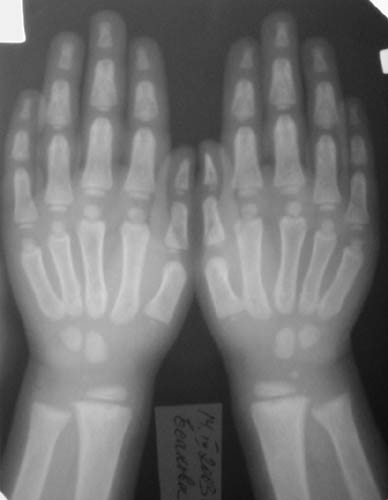

ТазКистиГолени

Девочка, 3 года 11 мес. Дз: Фосфатдиабет (витамин Д-резистентный рахит).

Жалобы на задержку роста. Общие анализы крови и мочи без особенностей.Биохимический анализ крови: билирубин 7,7, АЛТ 0,30, общий белок 73, креатин 0,061, щелочная фосфотаза 49%мл/г, K+ 4,4, Na+ 139, Ca++ 0,93, Ca общий 2,5.УЗИ органов брюшной полости: норма, печень увеличена, паренхима однородна, сосудистый рисунок сохранен. Рентгенологический возраст 2 года, хронологический возраст 4 года. Ранее рекомендована ЛФК, витамины, видеин.Рекомендации по лечению? Заранее благодарен! С уважением, А.В.Владзимирский Донецкий НИИ травматологии и ортопедии